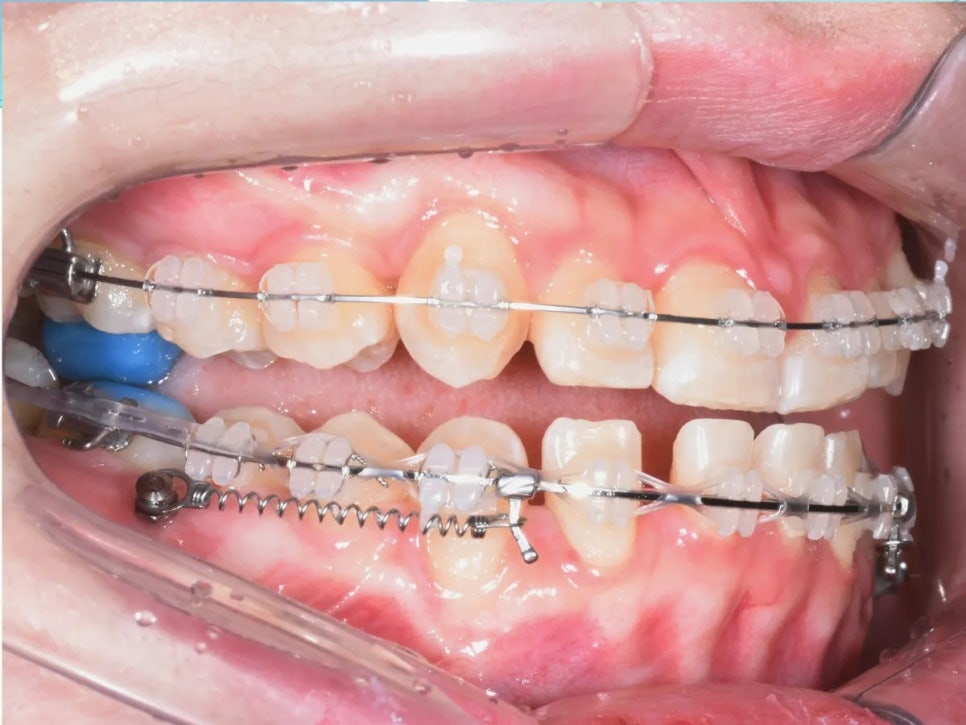

치료 2단계 – 미니스크류를 이용한 아랫니 후방 견인

위턱 쪽 작업이 진행되어 가면서, 아래턱에도 본격적인 치료를 시작했습니다. 아래턱에 미니스크류(아주 작은 나사 형태의 고정장치)를 심어서, 돌출된 아래 치열 전체를 뒤쪽으로 끌어당기는 방법을 사용했어요.

미니스크류는 뼈에 직접 고정되기 때문에 움직이지 않는 절대적인 기준점 역할을 합니다. 이 고정점을 이용해 스프링이나 체인으로 지속적인 힘을 가하면, 아래 치열이 조금씩 뒤로 이동하게 됩니다.

미니스크류를 활용하여 아래 치열을 뒤쪽으로 이동시키는 과정

정리하면, 위쪽 앞니는 앞으로, 아래쪽 치열은 뒤로 이동시키는 이중 효과로 반대교합을 교정하는 전략이에요. 이렇게 양쪽에서 동시에 접근하면 한쪽만 움직이는 것보다 훨씬 많이 위아랫니의 관계를 개선해줄 수 있습니다.

아래 치열 전체를 뒤로 보내는 중입니다